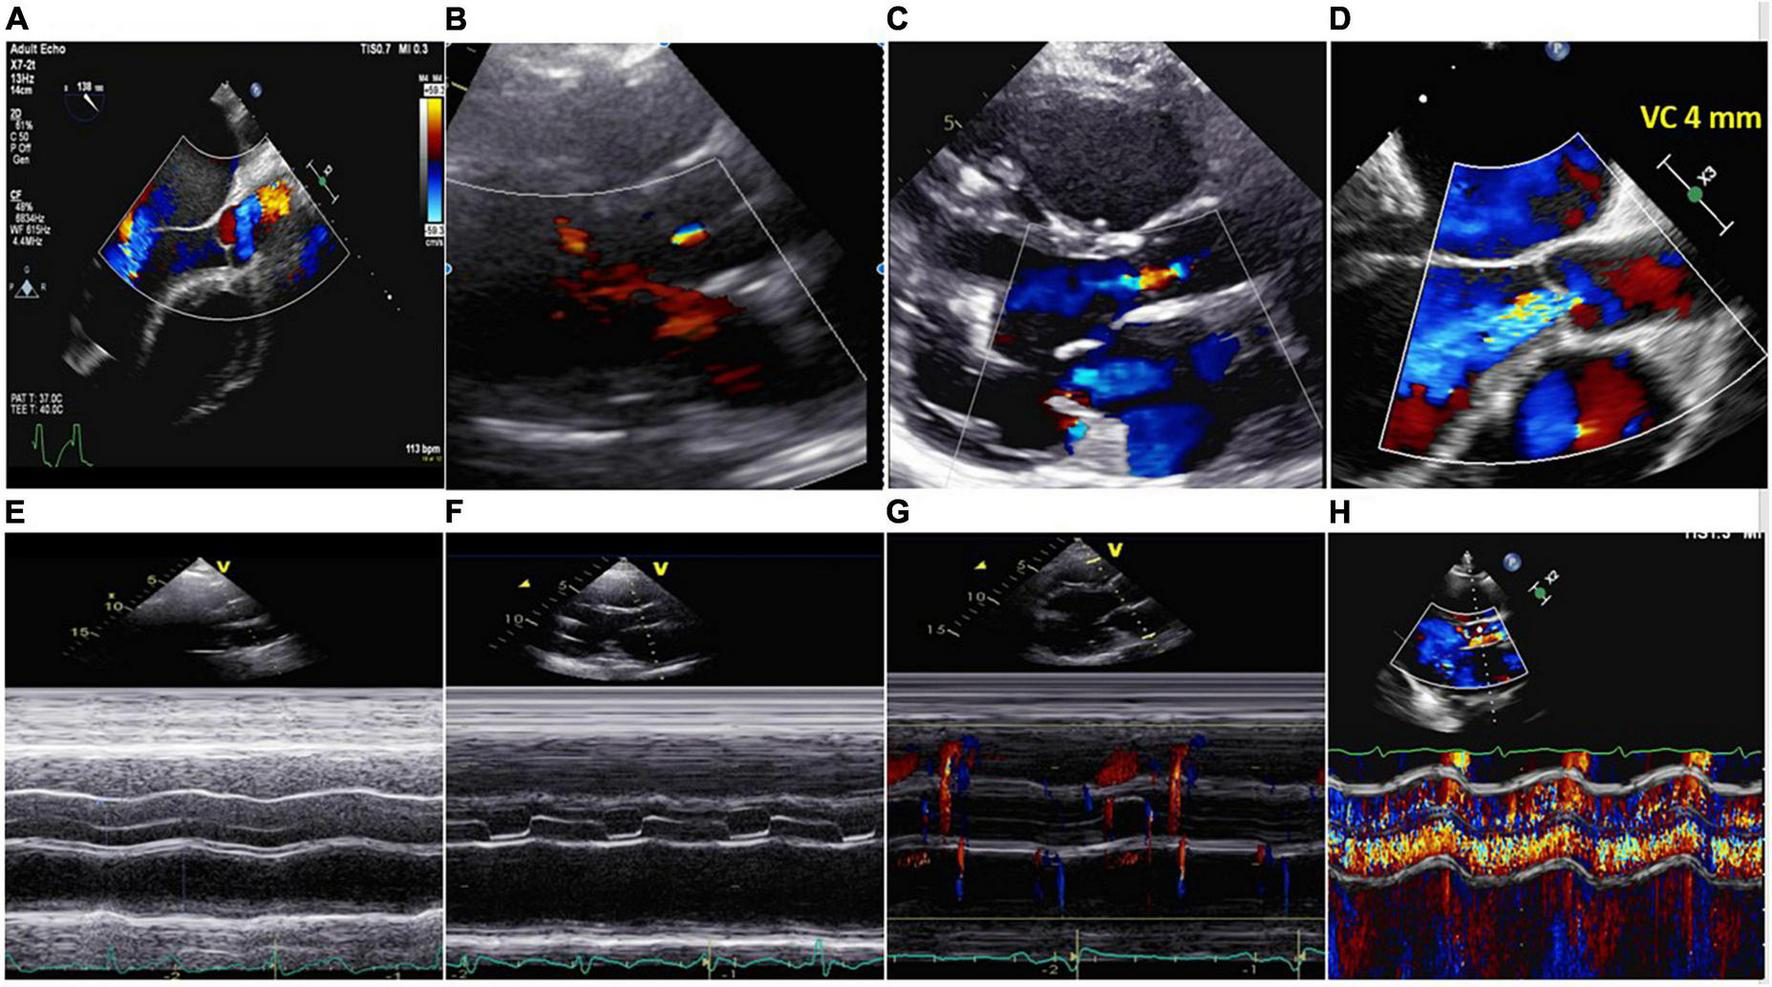

Importantly, the degree of AV opening can be significantly reduced or intermittent, depending on the LVAD speed. Ideally, LVAD support aims to open the aortic valve every two or three beats. M-Mode of the AV long-axis can help to quantify the degree of AV opening (intermittent opening, in which part of the cardiac cycle, extend AV opening) and if color is added also the AR characteristics (extent of AR into systolic period -electrical and mechanical-) It is suggested to acquire at low speed (25 mm/s) and at least 3–5 cardiac cycles.

Standard comprehensive echocardiography will be performed, with a particular emphasis on LV and RV dimensions, systolic function, inflow and outflow cannula interrogation, valvular apparatus included AV function (AR or aortic stenosis, AV normally open or closure time and its relationship with the cardiac cycle) (Figure 5). It is recommended to record 3–5 cycles. TTE should be performed according to the guidelines and remain consistent during the follow-up (77, 78). Since the quantification of AR in LVAD patients is quite challenging, a multiparametric approach is mandatory.

FIGURE 5

Upper part: (A) No aortic regurgitation (AR); (B) trivial AR; (C) mild AR; (D) severe continuous AR (VC 4 mm). Lower part: (E) Closed AV; (F) aortic valve open in end diastole and systole. No AR; (G) aortic valve opened in systole. No AR; (H) same patient of panel (D). M-Mode showing severe systolic-diastolic AR. The valve was closed during the cardiac cycle.